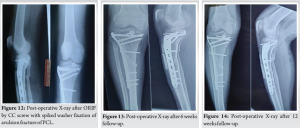

The insertion site for the cannulated cancellous (CC) screw was located and subsequently drilled with a cannulated drill bit. Ultimately, the avulsed fragment was secured by employing a 4 mm cannulated cancellous screw along with a spiked washer, which was screwed in place over the guide wire. The K-wire used for temporary fixation was then removed (Fig. 10-12).

At 6 weeks after surgery, the ROM was 20–60o. No instability was present in the posterior drawer test (Fig. 13).